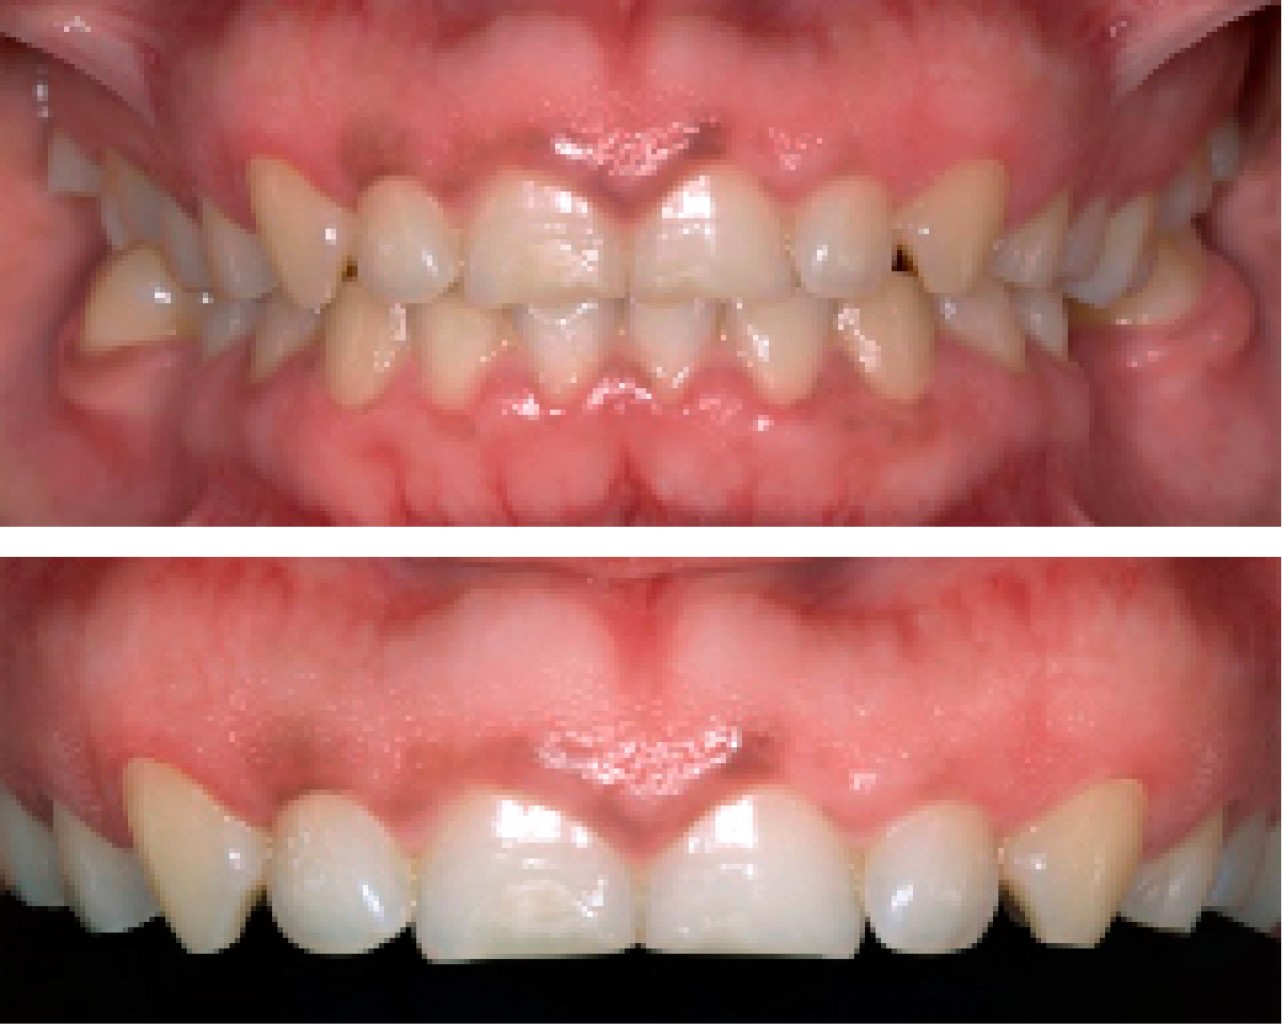

Paciente femenino de 24 años de edad, acude a atención odontológica y manifiesta en su motivo de consulta: "No me siento cómoda con la sonrisa". En la anamnesis realizada no refiere enfermedades patológicas, por lo que se considera como paciente aparentemente sana. En la evaluación clínica inicial se le realiza el sondeo periodontal dando como diagnóstico: erupción pasiva alterada tipo 1, subgrupo B en el sector anterior superior (del 1.3 a 2.3 según nomenclatura FDI) (Figura 1). El plan de tratamiento indicado es alargamiento de corona estético en una sola cita utilizando como herramienta radiológica de apoyo el CBCT con el objetivo de lograr precisión en la ubicación de los siguientes parámetros: tamaño de corona anatómica, longitud de UCE-cresta ósea y cantidad de tejido gingival a eliminar durante el procedimiento quirúrgico.

Se revisó a la paciente tras haber realizar el procedimiento quirúrgico, no presentó ninguna complicación, los tejidos gingivales con características normales, sin procesos inflamatorios y acorde con el proceso de cicatrización (Figura 5).